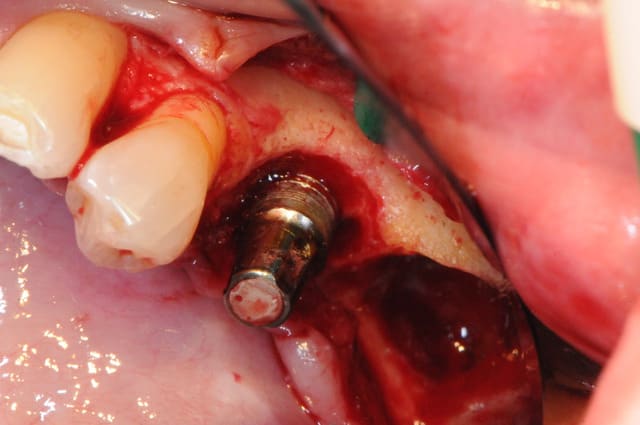

1-2-3 dépose du bridge

facile :) ça vient tout seul.

4 après un long moment de nettoyage, de curetage, de surfaçage implantaire, d'aeropolissage de l'implant, etc...

on fini enfin par arriver à ça.

ah oui, j'ai passé 2 fois un bon gros quart d'heure à gérer deux petites artères intra-osseuses de me..e qui m'ont vraiment pourri ma zénitude per-op.

de vraies petits geysers! ça doit faire dix ans que j'en avais pas eu des comme ça.

2-3 l'implant 35 que j'ai décidé de garder et donc de nettoyer.

pour le nettoyage, j'ai utilisé, en plus de l'aéropolissage, un écouvillons de chez STRAUMANN en titane.(à mon avis beaucoup trop souple et trop long.

y en a qui connaissent ?)